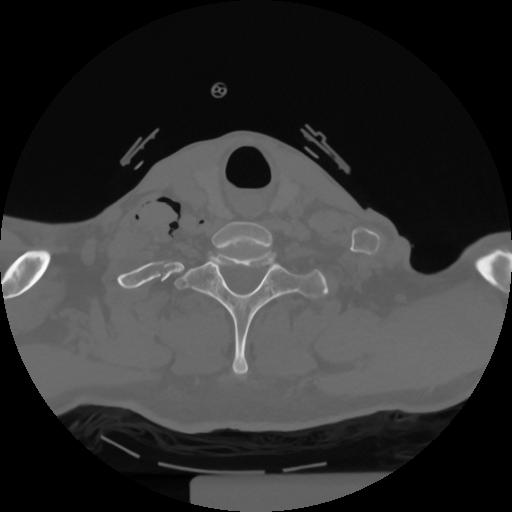

12 P.BLANDAS,,Vol,0.5,P.BLANDAS,,